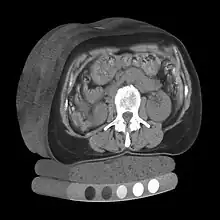

Tomography is imaging by sections or sectioning that uses any kind of penetrating wave. The method is used in radiology, archaeology, biology, atmospheric science, geophysics, oceanography, plasma physics, materials science, cosmochemistry, astrophysics, quantum information, and other areas of science. The word tomography is derived from Ancient Greek τόμος tomos, "slice, section" and γράφω graphō, "to write" or, in this context as well, "to describe." A device used in tomography is called a tomograph, while the image produced is a tomogram.

In many cases, the production of these images is based on the mathematical procedure tomographic reconstruction, such as X-ray computed tomography technically being produced from multiple projectional radiographs. Many different reconstruction algorithms exist. Most algorithms fall into one of two categories: filtered back projection (FBP) and iterative reconstruction (IR). These procedures give inexact results: they represent a compromise between accuracy and computation time required. FBP demands fewer computational resources, while IR generally produces fewer artifacts (errors in the reconstruction) at a higher computing cost.[1]

Volume rendering is a set of techniques used to display a 2D projection of a 3D discretely sampled data set, typically a 3D scalar field. A typical 3D data set is a group of 2D slice images acquired, for example, by a CT, MRI, or MicroCT scanner. These are usually acquired in a regular pattern (e.g., one slice every millimeter) and usually have a regular number of image pixels in a regular pattern. This is an example of a regular volumetric grid, with each volume element, or voxel represented by a single value that is obtained by sampling the immediate area surrounding the voxel.